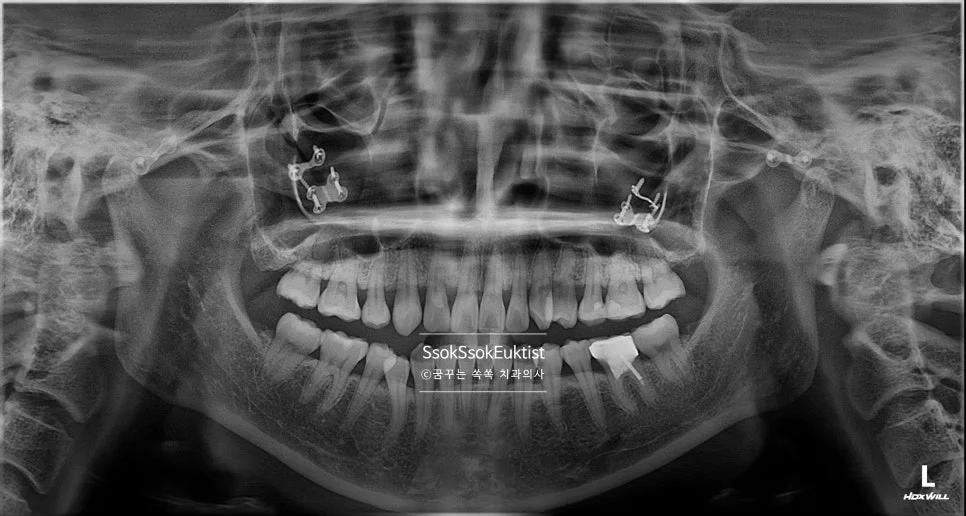

스케일링 진단 파노라마 방사선 사진

파노라마 X-ray — 스케일링 전 진단

보통은 스케일링도 수면 마취를 하겠다고 말씀하셔도, 진단을 해보면 잇몸 하방 치석, 충치, 발치할 사랑니, 임플란트 등 치료할 것들이 있어 수면마취를 통해 스케일링만 딱 진행하는 경우는 흔치 않은 것이 사실입니다.

치아 사이 충치를 가장 잘 볼 수 있는 교익 방사선(Bitewing X-ray) 사진으로도 치료가 필요한 치아는 찾을 수 없었는데요.

왼쪽 위 앞니의 치경부 우식이 하나 있어 이것을 제외하고는 정말 스케일링만 진행하면 되는 상황입니다.